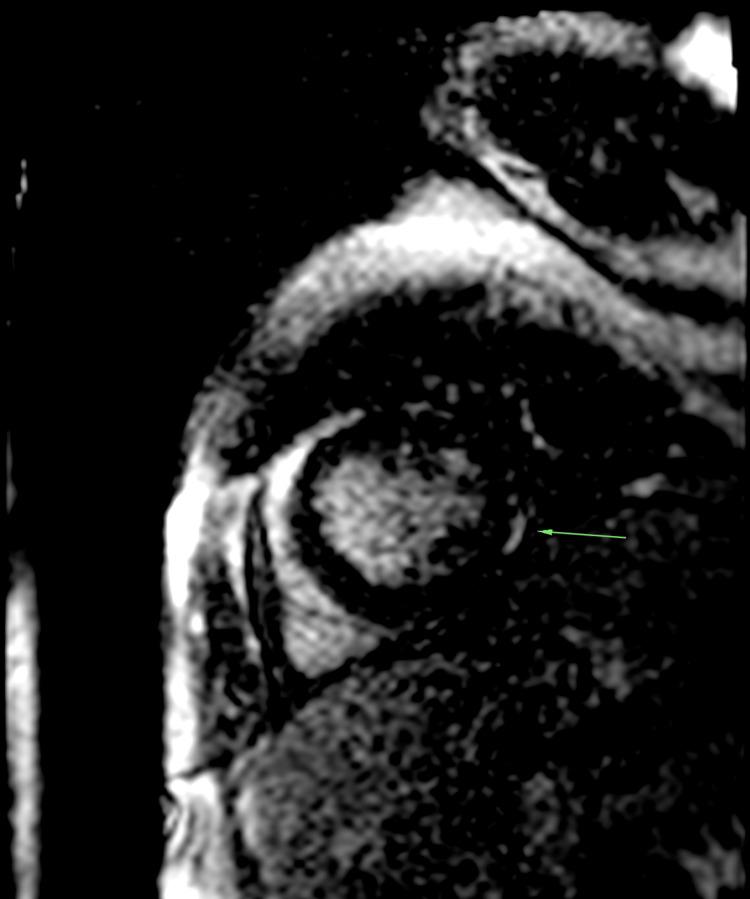

Cryoglobulinemic vasculitis is a rare small-vessel vasculitis leading to multi-organ dysfunction, often associated with chronic infections like hepatitis C virus (HCV), and autoimmune disorders. Most cases involve mixed monoclonal or polyclonal immunoglobulins, presenting symptoms such as purpura, arthralgias, and weakness. Severe organ involvement, particularly cardiac, is rare but potentially life-threatening. We report the case of a 48-year-old woman without prior medical history who presented with acute dyspnea, generalized petechial purpura, and signs of global heart failure. Imaging and laboratory findings indicated cardiomegaly, pericardial effusion, and significant nephrotic syndrome with renal failure. The diagnosis of cryoglobulinaemia was confirmed through histology and serology, showing monoclonal IgM with kappa hypergammaglobulinaemia and complement consumption. Treatment included various immunosuppressants, corticosteroids, and rituximab combined with renal replacement therapy. Following the initiation of treatment and proper management of heart failure, the patient's condition significantly improved. Cardiac involvement in cryoglobulinemic vasculitis, though rare, can lead to severe heart failure. This often involves necrotizing vasculitis of the coronary arteries or systemic inflammation damaging the cardiac muscle, as observed here. Cardiac manifestations with immunosuppressive therapy are reversible despite a poor long-term prognosis for patients with cardiac lesions. In conclusion, cryoglobulinemic vasculitis has a grim prognosis due to its multi-organ impact and the severity of the lesions. Early and aggressive treatment is essential to manage life-threatening acute presentations, even before confirming the diagnosis biologically or histologically.

冷球蛋白血症性血管炎是一种罕见的小血管血管炎,可导致多器官功能障碍,常与丙型肝炎病毒(HCV)等慢性感染以及自身免疫性疾病相关。大多数病例涉及混合性单克隆或多克隆免疫球蛋白,表现为紫癜、关节痛和乏力等症状。严重的器官受累,尤其是心脏受累,虽罕见但可能危及生命。我们报告一例48岁无既往病史的女性,她出现急性呼吸困难、全身性瘀点性紫癜及全心衰体征。影像学和实验室检查结果显示心脏扩大、心包积液以及伴有肾衰竭的显著肾病综合征。通过组织学和血清学检查确诊为冷球蛋白血症,显示单克隆IgM伴κ轻链高球蛋白血症及补体消耗。治疗包括多种免疫抑制剂、糖皮质激素以及利妥昔单抗联合肾脏替代治疗。在开始治疗并对心力衰竭进行恰当管理后,患者病情显著改善。冷球蛋白血症性血管炎中的心脏受累虽罕见,但可导致严重心力衰竭。如此处所见,这通常涉及冠状动脉坏死性血管炎或系统性炎症对心肌的损害。尽管心脏病变患者的长期预后不佳,但免疫抑制治疗后的心脏表现是可逆的。总之,冷球蛋白血症性血管炎因其对多器官的影响及病变的严重性,预后严峻。即使在生物学或组织学确诊之前,早期积极治疗对于处理危及生命的急性表现至关重要。